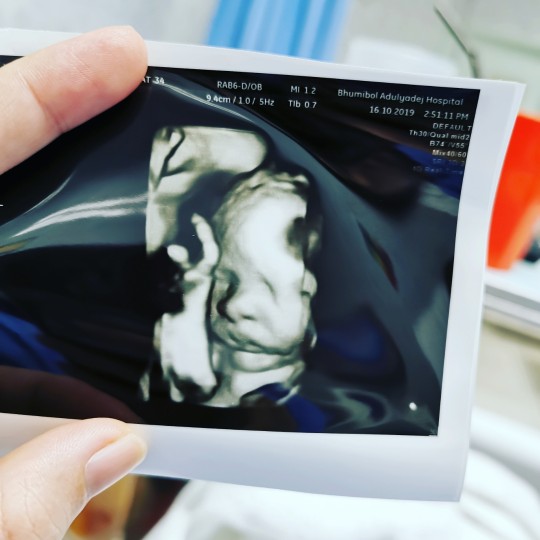

มีบ้านไหนซาวด์แล้วจมูกโด่งแบบนี้มั้ยคะ ออกมาจมูกน้องโด่งแบบนี้รึเปล่า? นี่คุณหมอบอกโด่งมาก?

จมูกโด่งมากเลย มีชัยไปกว่าครึ้ง 555

โอ้โหโด่งตั้งแต่ในใบซาวด์เลยค่ะ